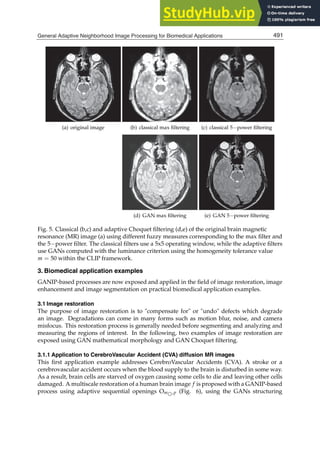

minimization (WACFM, WAPM) and on statistical inference (EBWA.1, EBWA.3, EBWA.C,

SEBWA) together with fuzzy extensions, which use the fuzzy partition the signal cycle as well

as using fuzzy numbers as coefcients of weight vector. The adaptation of SEBWA method to

384 Applied Biomedical Engineering